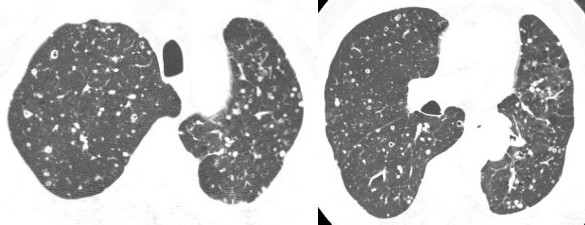

病例1:重症肺炎

男,28岁,发热一周,咳嗽气短2天。虽然很年轻,但是住院时的病情很严重。虽然右上肺有斑片实变影,但两肺有广泛不规则的结节。CT显示的大多数边界不清晰,边缘有些类似磨玻璃影,右上叶可以看到磨玻璃样改变。这是不规则结节,不像肿瘤性病变呈边界比较清楚、比较圆的结节。这个病人的诊断是重症肺炎,调整治疗后效果很好。

病例2:曲霉菌感染

血液病病人,治疗后发烧。两肺多发结节,大的团块可以看到充气支气管征,实际上这是一个实变影,有大肿块和小结节。血液病的病人治疗后,如果出现这样的结节,首先想到真菌感染。这个病人最后诊断是曲霉菌感染。